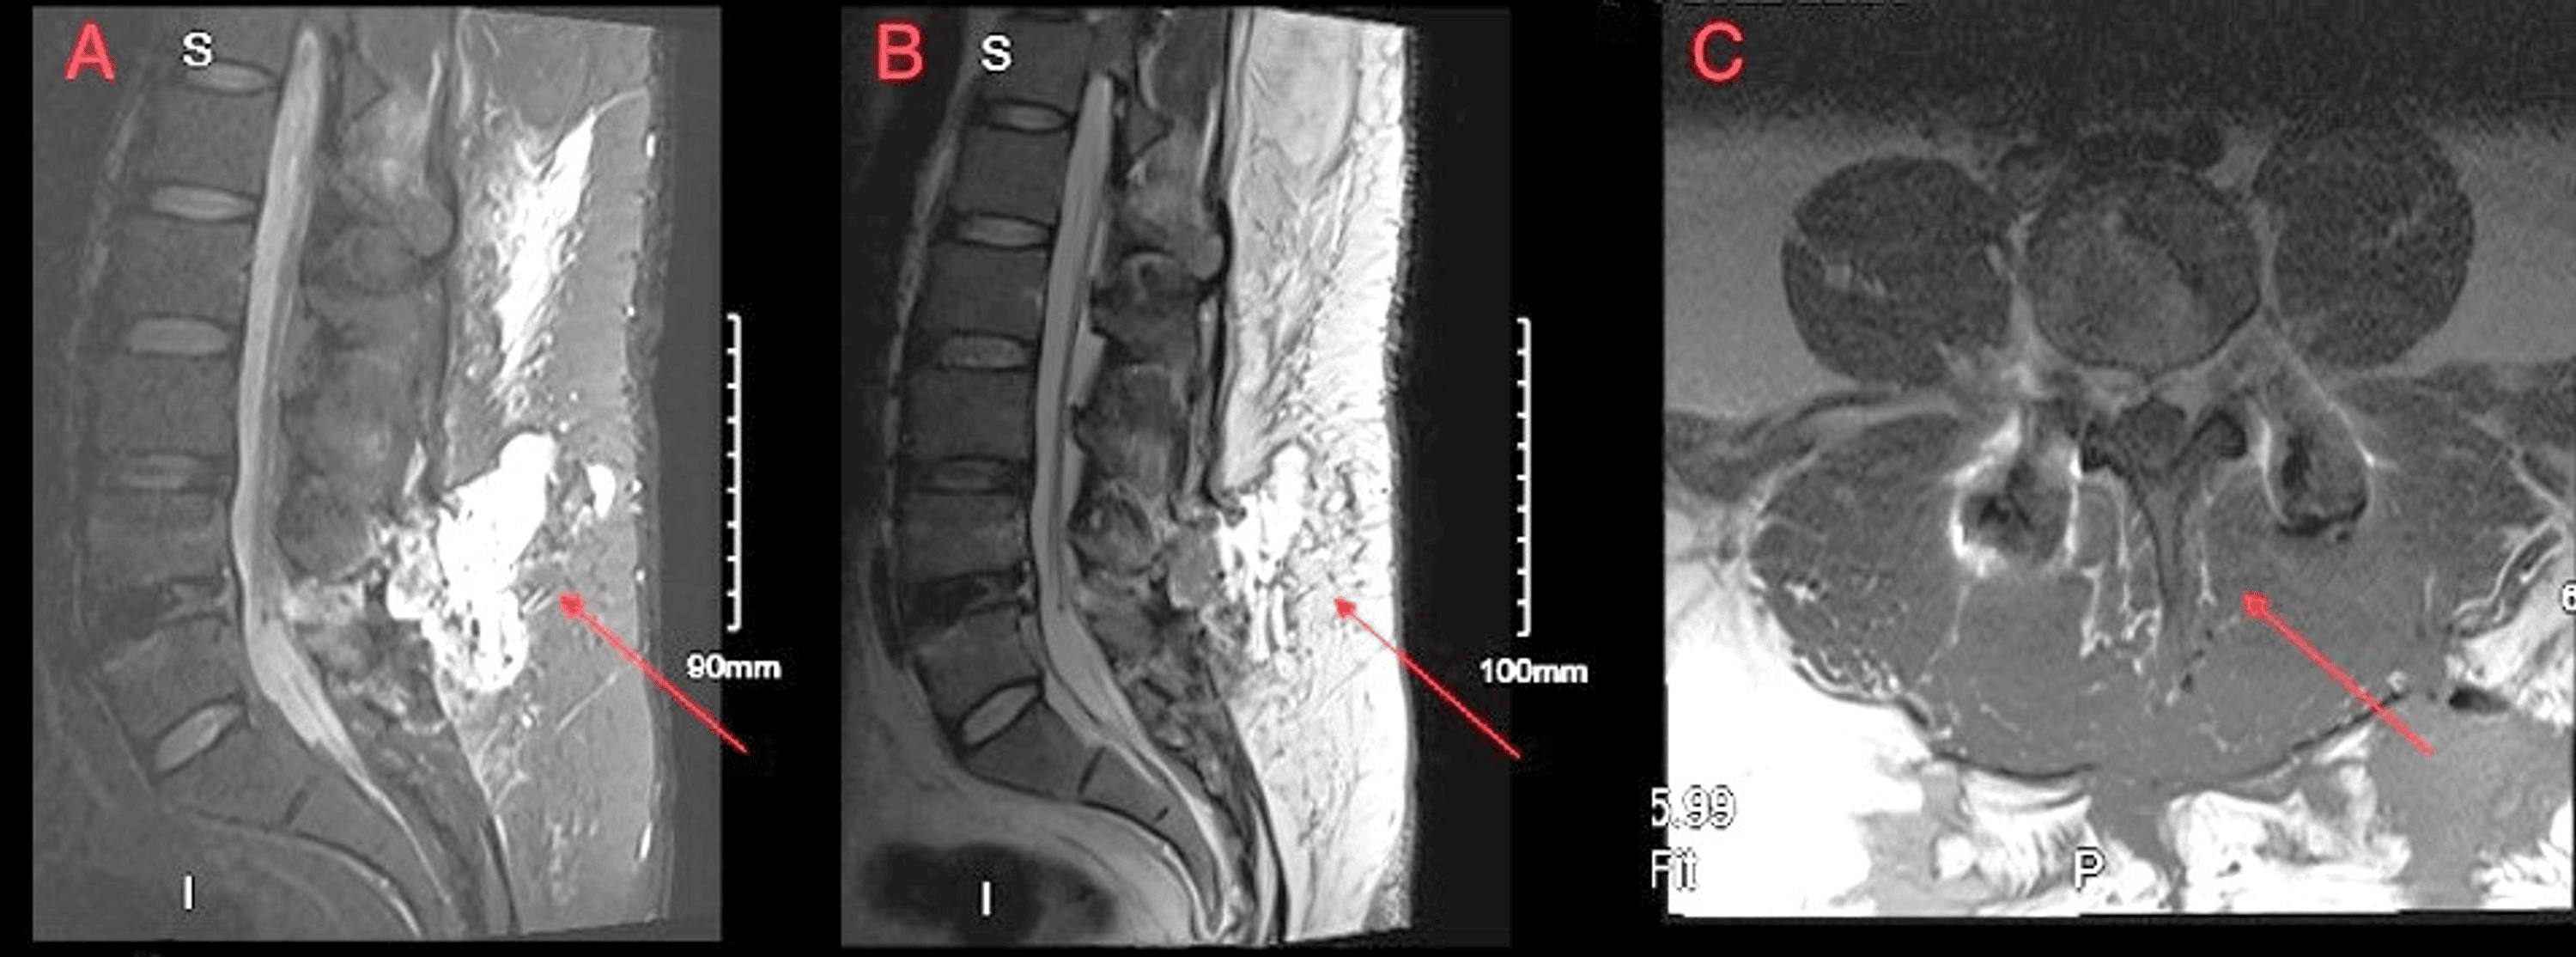

Cureus Management of Superrefractory Postoperative Lumbar Coronal Lumbar Mri The main features on mri of the lumbar spine include features demonstrating underlying inflammation and its effects, such as bone marrow oedema, squaring of the vertebral bodies (romanus lesions), syndesmophyte formation, ankylosis and erosions (figure 5). The purpose of this study is to determine the value of adding a coronal stir sequence to the routine mri protocol in patients. This. Coronal Lumbar Mri.